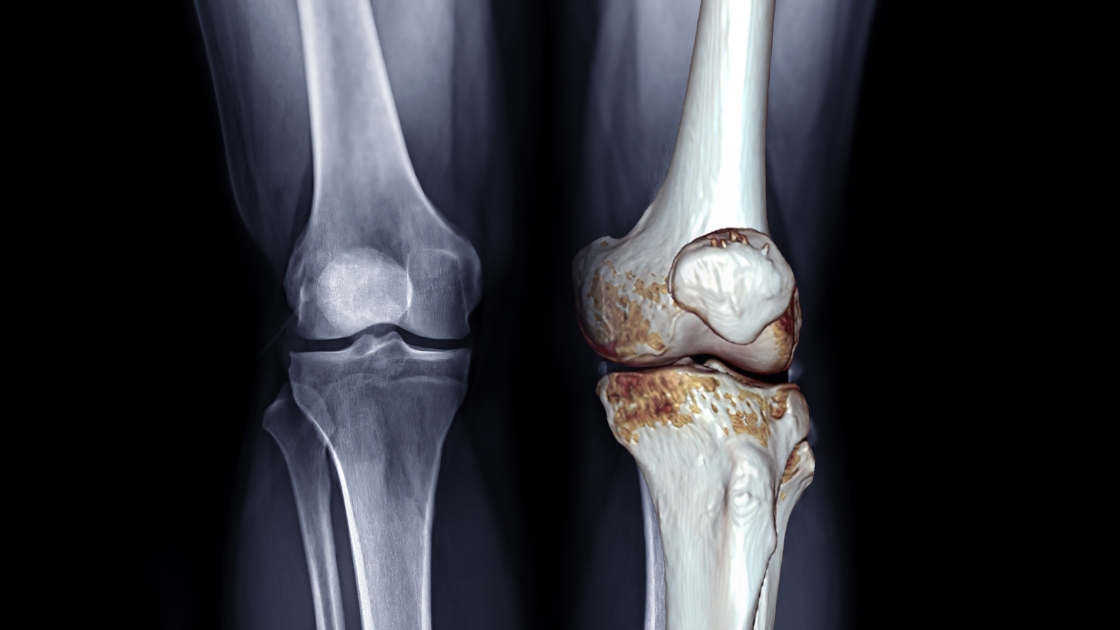

O diagnóstico é feito por avaliação clínica com ortopedista, que analisa os sintomas, histórico do paciente e realiza exames físicos. A confirmação costuma ser feita por radiografias, que revelam o estreitamento do espaço articular, presença de osteófitos (bicos de papagaio) e outras alterações típicas da artrose. Em alguns casos, exames como ressonância magnética são utilizados para avaliar o estado da cartilagem com mais detalhes.